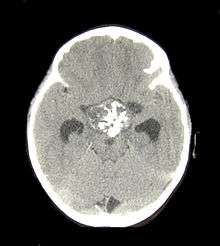

If one of these tests shows a deficiency of hormones produced by the pituitary, magnetic resonance imaging (MRI) scan of the pituitary is the first step in identifying an underlying cause. MRI may show various tumors and may assist in delineating other causes. Tumors smaller than 1 cm are referred to as microadenomas, and larger lesions are called macroadenomas.[1] Computed tomography with radiocontrast may be used if MRI is not available.[7] Formal visual field testing by perimetry is recommended, as this would show evidence of optic nerve compression by a tumor.[7]